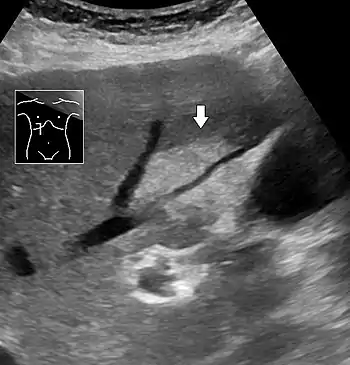

On abdominal ultrasonography, steatosis is seen as a hyperechoic liver as compared to the normal kidney.

Liver steatosis (fatty liver disease) as seen on MRI. Multiecho MR sequence in a healthy liver (top row) and a liver with severe steatosis (bottom row) are shown. In the healthy liver, the signal does not vary much in the different echoes. In the steatotic liver, the signal varies greatly between in and out phase echoes. Algebraic combination of these images can be used to accurately quantify liver steatosis. Abdominal ultrasonography with the liver and kidney side by side (left image) may give a false impression of hyperechogenic liver, so it's preferably done with the organ borders facing the ultrasound probe (right image, of the same case).

Abdominal ultrasonography with the liver and kidney side by side (left image) may give a false impression of hyperechogenic liver, so it's preferably done with the organ borders facing the ultrasound probe (right image, of the same case). Abdominal ultrasonography of focal steatosis. It is distinguished from a tumor by not compressing the hepatic vein.

Abdominal ultrasonography of focal steatosis. It is distinguished from a tumor by not compressing the hepatic vein.